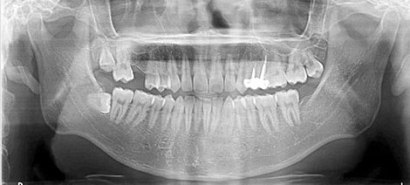

因長期缺失第一大臼齒而導致第二大臼齒歪斜,矯正介入治療將牙齒扶正騰出足夠的空間後 ,再透過植牙將全口重建。

患者全口X光

治療前

治療後